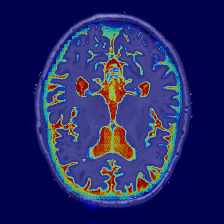

Figure 4: Qualitative comparison of segmentation results on the OASIS-1 and MRBrainS13 datasets. Our proposed PCMambaNet (last column in each set) demonstrates superior performance in boundary delineation and structural coherence compared to several strong baselines. Note our model’s ability to produce segmentations that more faithfully match the ground truth (GT), with noticeably fewer false positives and more accurate handling of complex anatomical regions. Red arrows highlight areas where the advantages of our method are particularly evident.

Qualitative Results. Qualitative results, presented in Figure 4, visually corroborate the quantitative findings and highlight the architectural advantages of PCMambaNet. In the full-data regime (left panel), baseline models often struggle with fine boundaries, producing noisy or incomplete segmentations. In contrast, our model leverages the PPM to focus on critical locations, which then allows the CRN to accurately delineate complex contours that are highly consistent with the ground truth. The superiority of our approach is particularly evident in data-limited conditions (right panel). While competing models yield overly smooth results that miss fine-grained, infiltrative details, our model’s “predict-then-correct” strategy enables it to effectively capture these complex boundary features. Consequently, PCMambaNet produces visually sharper and more anatomically plausible segmentation results, especially in challenging, low-data scenarios.